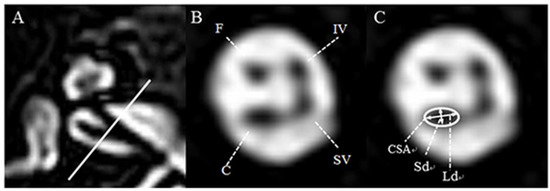

IAC imaging was performed by a 3T MRI scanner (Achieva and Ingenia; Philips, Best, Netherlands), equipped with a SENSE head coil (Philips Healthcare) for signal reception. On the basis of T2-weighted turbo spin-echo acquisition (TR, the repetition time/TE, the echo time: 7395/120 ms; flip angle: 90°; slice thickness: 0.7 mm; no slice gap; field of view (FOV): 100 × 100 mm2; voxel size: 0.4 × 0.4 × 0.4 mm3), the oblique sagittal images that directly showed the presence of nerves in the IAC were reformatted in planes perpendicular to the course of the nerve in the midpoint of IAC of axial images (Figure 1A). On the oblique parasagittal image of the unaffected ear, the facial nerve (FN) lies superiorly, with the cochlear nerve (CN) inferior to it, within the anterior aspect of the canal. The superior (SVN) and inferior vestibular nerve (IVN) lie posteriorly (Figure 1B). The lengths of the major axis (long diameter, Ld) and the minor axis, which is perpendicular to the major axis (short diameter, Sd) of CN, on the oblique parasagittal images of both the unaffected and affected ears were measured to the nearest 0.1 mm by two neuro-radiologists blinded to all subjects’ information using a software on the PACS workstation combined with sharpening and zooming (Infinitt, Seoul, South Korea). The cross-sectional area (CSA) of CN was also measured as elliptical regions of interest (ROI) on the basis of Sd and Ld (Figure 1C).

The mean of Ld, Sd, and CSA in the unaffected ears from the present study were 1.19 ± 0.13 mm, 0.95 ± 0.16 mm, and 0.89 ± 0.18 mm2, respectively (Figure 2).

The CN status was classified in accordance with the presence or the size of CN: (1) ‘absent CN’ refers to the a parasagittal oblique image with no visible CN; (2) ‘small CN’ is defined as when CN of the affected ear is optically smaller than FN and the values of Ld, Sd, and CSA were all less than those corresponding to one standard deviation from the mean of the unaffected ear (Ld < 1.06 mm; Sd < 0.79 mm; CSA < 0.71 mm2); (3) ‘indeterminate CN’ is defined as when CN is optically similar to the FN in size but meets all diagnostic criteria values for ‘small CN’. In this study, CND included ‘absent CN’, ‘small CN’, and ‘indeterminate CN’ as defined according to their criteria described above. Based on IAC MRI, anatomical abnormalities were reviewed with regard to structural specificities, including CN integrity, inner ear (cochlea, vestibule, endolymphatic duct, semicircular canals), and brain lesions.

Figure 1. Axial and oblique sagittal three-dimensional (3D) T2-VISTA MRI of the normal ear at the level of the internal auditory canal. (A) The oblique sagittal image was established with the baseline perpendicular to the course of the nerve in the midpoint of internal auditory canal (IAC) of an axial image. (B) In the anterior aspect of the IAC, the facial nerve lies superiorly, whereas the cochlear nerve lies inferiorly. In the posterior aspect of the IAC, the superior vestibular nerve lies superiorly, whereas the inferior vestibular nerve lies inferiorly. (C) For the evaluation of cochlear nerve integrity, the short diameter (Sd, mm), long diameter (Ld, mm), and cross-sectional area (CSA, mm2) were measured as indicated. F: facial neve, C: cochlear nerve, SV: superior vestibular nerve, IV: inferior vestibular nerve.